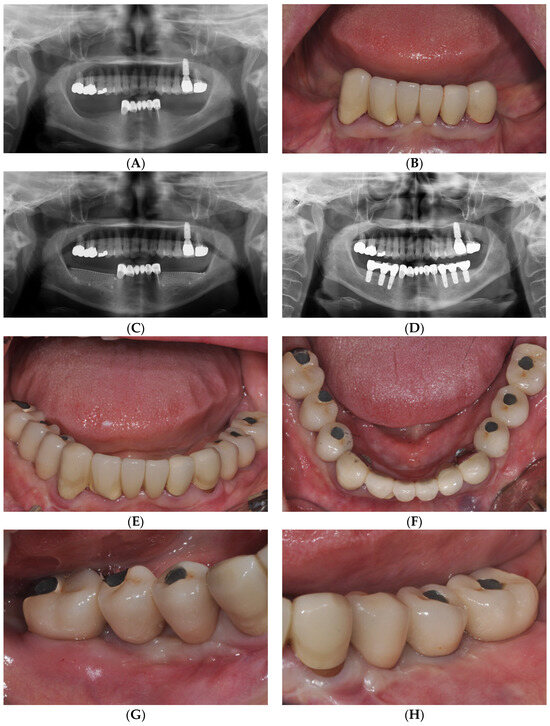

Figure 1 from Technical Note on Vestibuloplasty Around Dental Implants Dental Code For Vestibuloplasty Vestibuloplasty is a term representing numerous procedures with a common goal: Increased alveolar ridge or bone height relative to. Vestibuloplasty is a surgical procedure to improve the fit of a prosthetic device. The three main techniques to deepen the vestibule are: Vestibuloplasty is a surgical procedure designed to restore alveolar ridge height by lowering muscles attaching to the alveolar bone.. Dental Code For Vestibuloplasty.